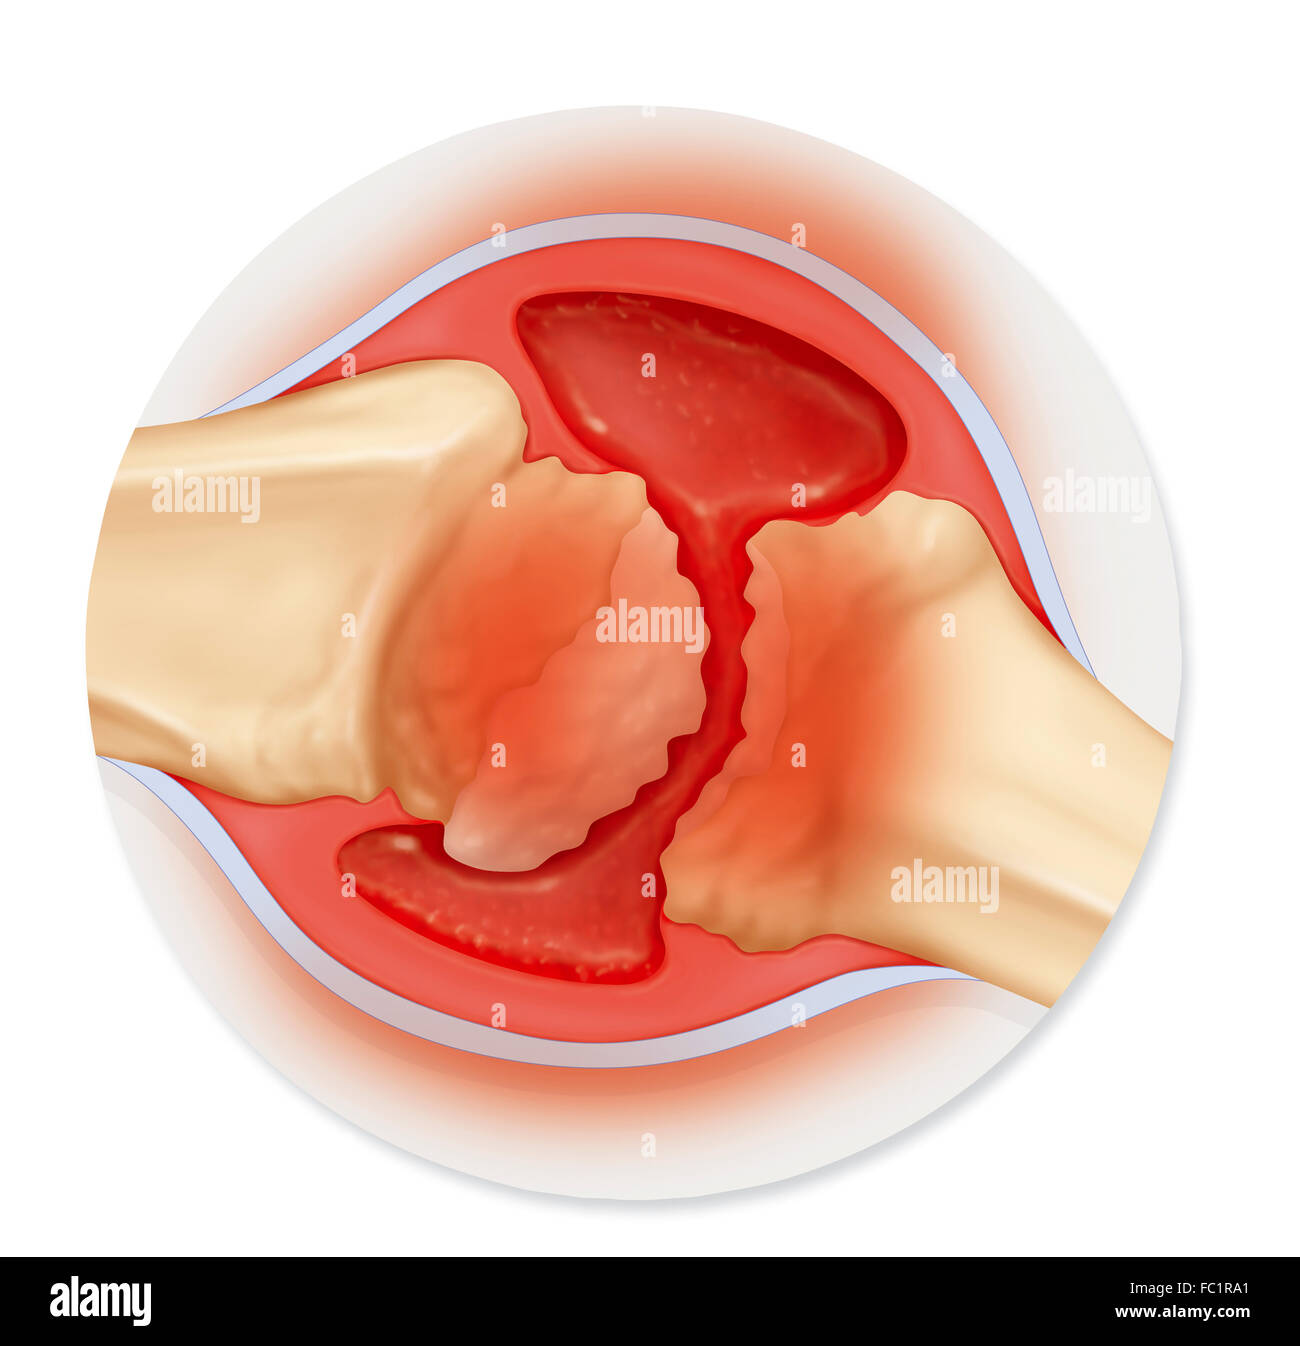

RHEUMATOID ARTHRITIS, DRAWING Stock Photohttps://www.alamy.com/image-license-details/?v=1https://www.alamy.com/stock-photo-rheumatoid-arthritis-drawing-93467992.html

RHEUMATOID ARTHRITIS, DRAWING Stock Photohttps://www.alamy.com/image-license-details/?v=1https://www.alamy.com/stock-photo-rheumatoid-arthritis-drawing-93467992.htmlRMFC1RAG–RHEUMATOID ARTHRITIS, DRAWING

RHEUMATOID ARTHRITIS, DRAWING Stock Photohttps://www.alamy.com/image-license-details/?v=1https://www.alamy.com/stock-photo-rheumatoid-arthritis-drawing-93467977.html

RHEUMATOID ARTHRITIS, DRAWING Stock Photohttps://www.alamy.com/image-license-details/?v=1https://www.alamy.com/stock-photo-rheumatoid-arthritis-drawing-93467977.htmlRMFC1RA1–RHEUMATOID ARTHRITIS, DRAWING